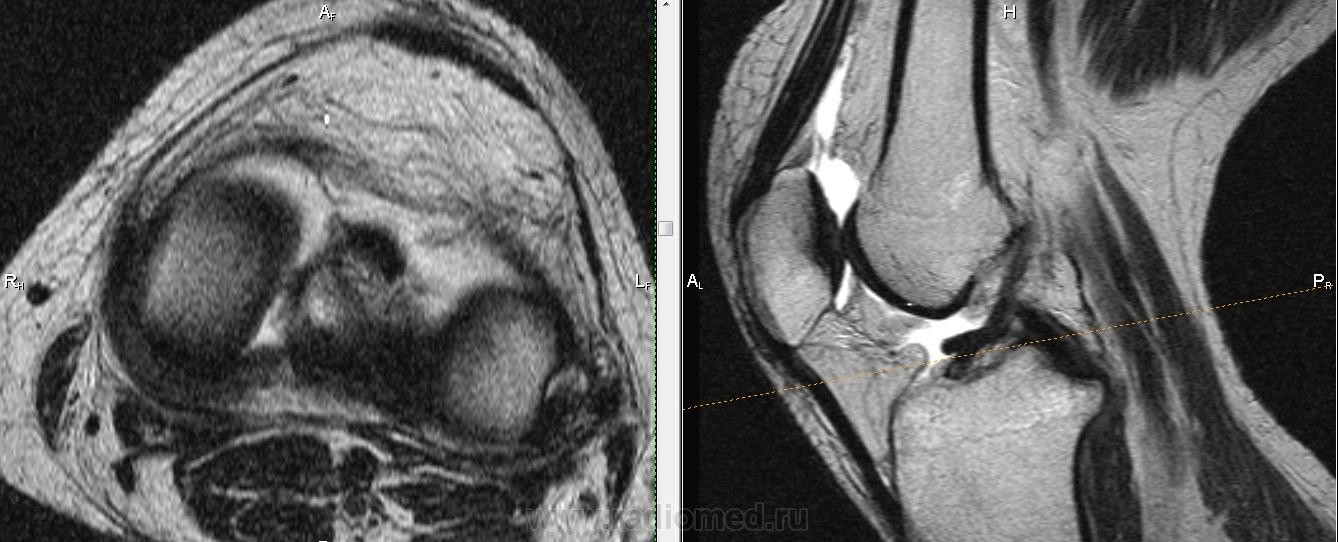

Падение с велосипеда. Вперед выступает фрагмент ПКС?

Не очень понятно, Михаил Александрович.Как-будто бы симптом "двойной  крестообразной связки", но не совсем похоже: при  этом  связка как-бы дугообразно идет.И мениски визуально вроде бы целы.Не может это быть фрагментом  переднего рога мениска?

Трудно сказать, на фрагмен мениска более похоже. Да и ПКС не отечная и внутренний мениск какой-то дефицитный. Если вопрос о цесостности ПКС обычно косая проекция выручает.

Думаю , тут фрагмент   переднего рога и части тела  латерального мениска ,  он(фрагмент) совсем  оторвался и уплыл кпереди .